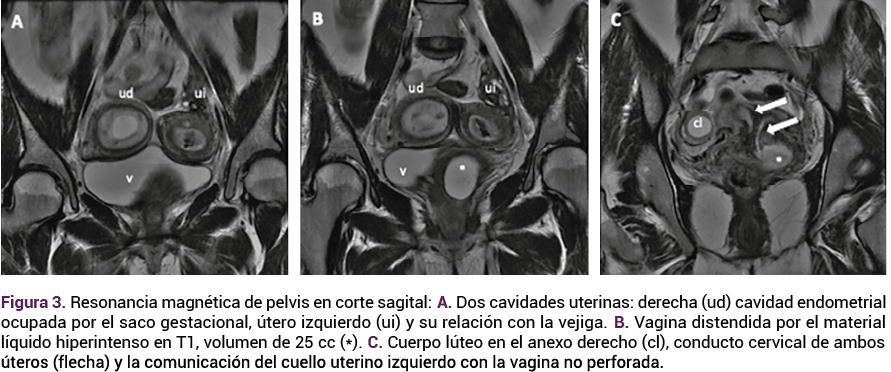

Durante la hospitalización no se registraron alteraciones en los estudios de laboratorio de fase aguda que indicaran un proceso infeccioso sistémico; sin embargo, por las características de la secreción, se indicó un esquema antibiótico doble de amplio espectro, con adecuada evolución clínica que ameritó el alta del hospital. El control prenatal continuó en la consulta externa de obstetricia, donde se solicitó otra resonancia magnética de control para valoración de la colección derecha; el estudio reportó la ausencia de colección aparente en la vagina izquierda. Figura 4

Figura 4.